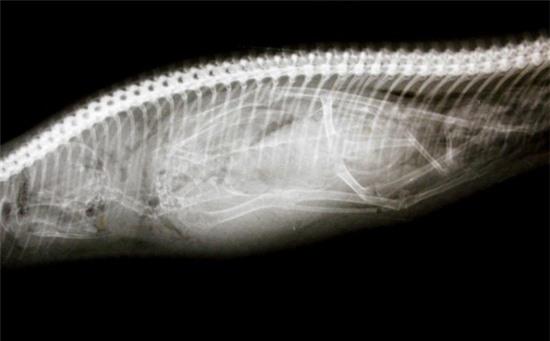

Khóc thét trước những dị vật nguy hiểm nằm gọn trong dạ dày thú cưng 1

Con dao đi săn trong số những đồ vật khác nằm trong bụng của chú chó Izzy.